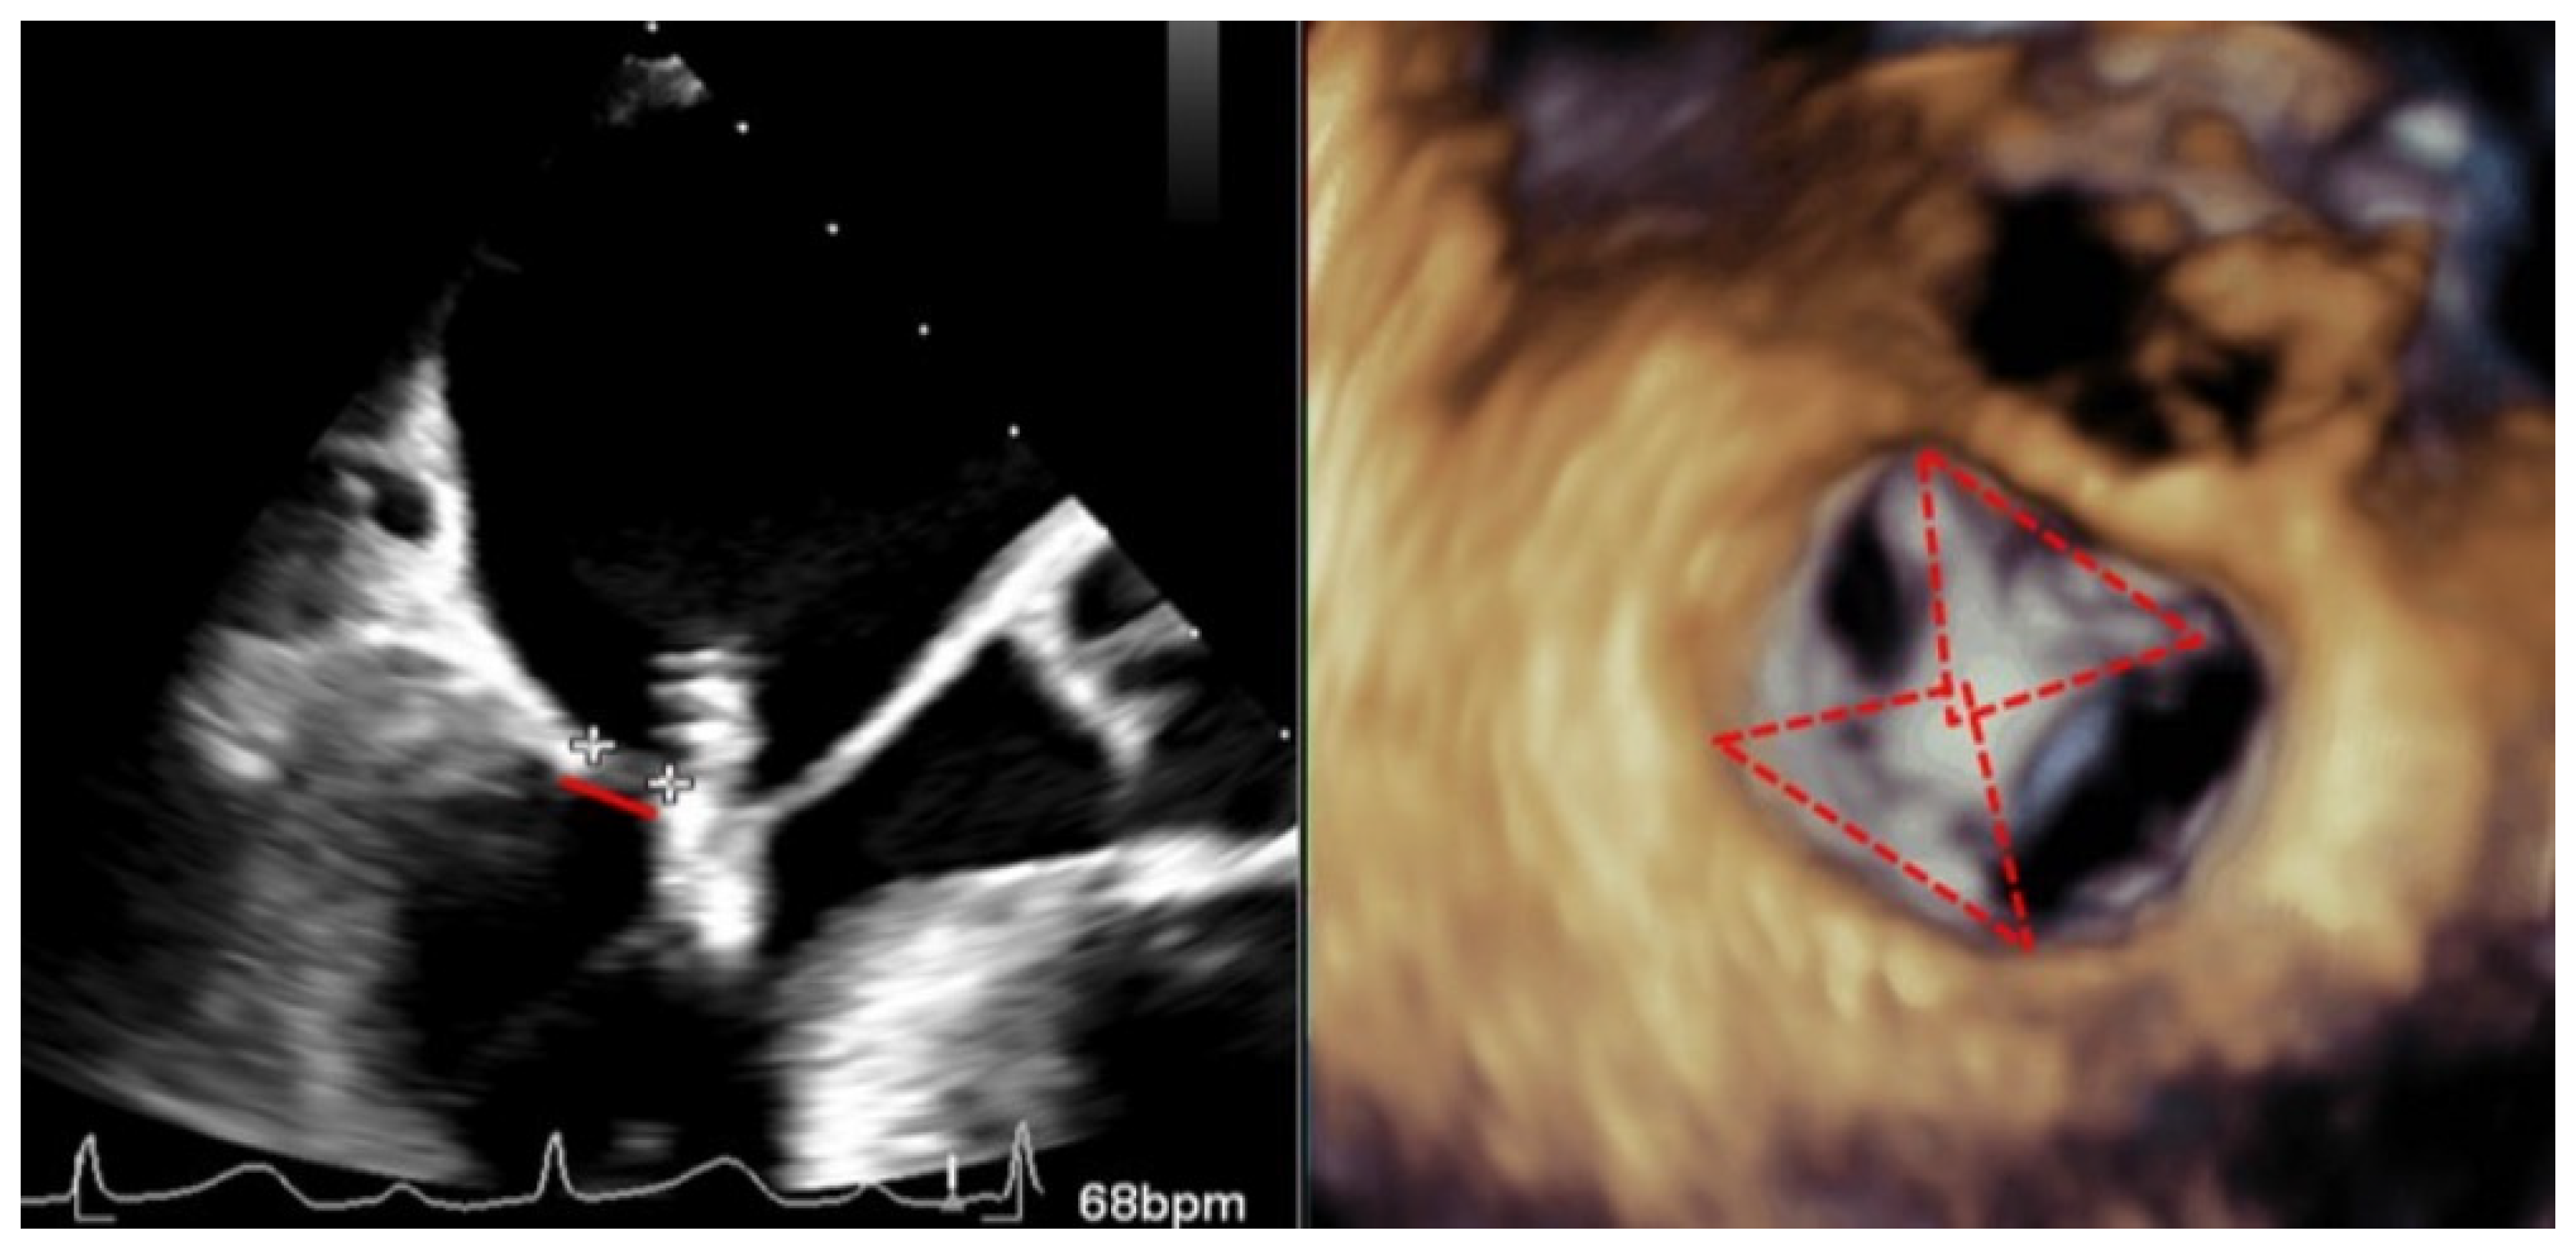

Figure 4.

Transesophageal echocardiogram during grasping. (Left) Two-dimensional transesophageal echocardiogram in the view of the left ventricular outflow tract, showing the tension of both leaflets and the measurement of the posterior leaflet introduced in the clip (red line delimited by plus sings). (Right) En-face 3D transesophageal echocardiogram view of the mitral valve with a clip between A2 and P2 with 2 symmetrical pyramids (red dotted lines).

Recently, the introduction of biplane images has facilitated the assessment of clip attachment due to the acquisition of simultaneous perpendicular views. Different authors have demonstrated that the additional use of 3D-TEE for the assessment of clip attachment may contribute to a reduced rate of subsequent clip complication [3]; therefore, the amount of both leaflets introduced into the clip must be assessed in a 3D enface view observing the amplitude of the inserted tissue and the formation of two pyramids whose vertex must be at least as wide as the clip (Figure 4). Checking a precise rotation of the device by 3D-TEE to avoid asymmetric grasping is another important step to avoid this complication, and, in addition, multiple leaflet grasps may lead to leaflet injury and should be avoided if possible.